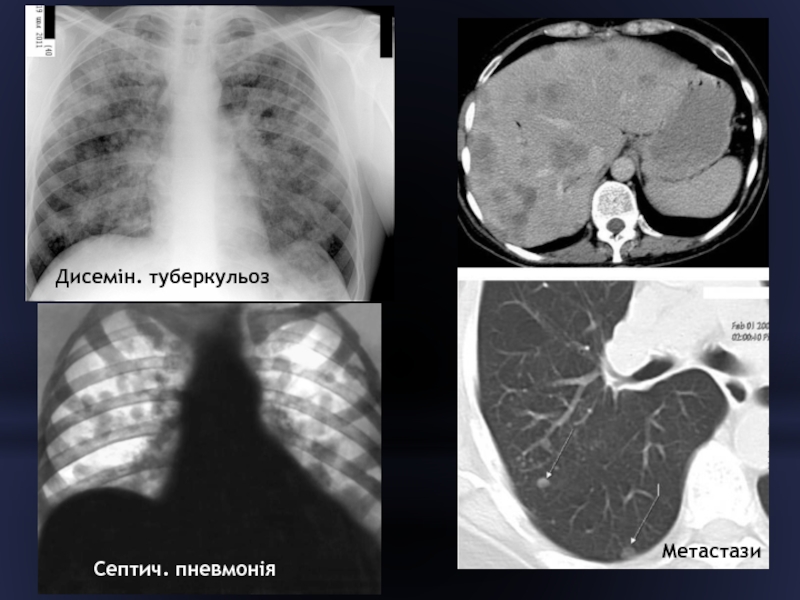

Слайд 43ДИСЕМІНАЦІЯ ВОГНИЩЕВИХ ТІНЕЙ

- розсіювання вогнищевих тіней протягом

одного або декількох легеневих полів

Часті

причини:

дисемінований туберкульоз легень

вогнищева пневмонія при сепсисі

метастази

Рідше: - пневмоконіози

- ацинозно-дольковий набряк

- гемосидероз

- саркоїдоз

- альвеоліти

Слайд 44Дисемін. туберкульоз

Септич. пневмонія